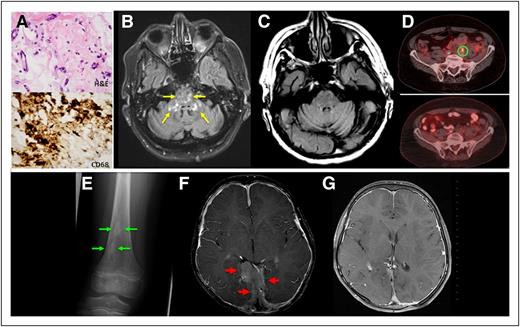

Perinephric tissue. Patient 1 with a CD68+ histiocytic infiltrate with admixed fibrosis (A). Axial T2-fluid attenuation inversion recovery MRI images demonstrate scattered lesions in the brainstem and cerebellar peduncles (yellow arrows) (B), and these are resolved after 6 months of treatment (C). A representative FDG-avid (SUV 3.1) periarterial lesion (D, upper) has resolved to background uptake (D, lower). Sclerotic lesions from the distal femur of patient 2 (E). Expansile meningeal infiltrations are demonstrated by axial postgadolinium T1-weighted MRI scan (red arrow) before treatment (F) and then are resolved 2 years into anakinra therapy (G).

Patient 1, a 68-year-old man, had developed diabetes insipidus 10 years prior, although cranial imaging was not performed at that time. Later, he was evaluated for ataxia and dysarthria as well as progressive bone pain in both legs, fatigue, and night sweats. Enhanced magnetic resonance imaging (MRI) of the brain was performed and demonstrated (Figure 1B) scattered areas of T2-prolongation in the pons and middle cerebellar peduncles bilaterally. Computed tomography and FDG-PET demonstrated hypermetabolic infiltrations in the perinephric, periaortic, and perisplenic regions as well as avid, symmetric, sclerotic lesions in the femurs and tibia. Percutaneous needle biopsy of perinephric soft tissue demonstrated a mixed nonxanthomatous inflammatory/histiocytic infiltrate with marked CD68 immunoreactivity (Figure 1A), and admixed fibrosis. Biopsy of a tibial lesion demonstrated a xanthomatous histiocytic infiltrate, consistent with ECD. CD1a immunohistochemistry was not performed in light of the clinical phenotype highly consistent with ECD and also to preserve material for genotyping. Targeted sequencing demonstrated a MAP2K1C121S mutation in lesional tissue. Treatment with IFN-α was deferred because of the patient’s wish to avoid its known toxicities; therefore, treatment was initiated with anakinra, 100 mg injected daily. Clinical symptoms (constitutional and neurologic) improved over the coming weeks, and sequential MRI scans of the brain up to 6 months on treatment demonstrated resolution of T2 hyperintensities in the brainstem (Figure 1C). FDG-PET demonstrated reduction in hypermetabolism of abdominal and osseous infiltrates (Figure 1D). No toxicities have been observed, and the patient continues anakinra therapy, currently for 9 months.

Patient 2, a 7-year-old boy, presented with several weeks of lethargy, dizziness, worsening hearing loss, and facial asymmetry. He was found to have a left facial palsy on physical examination. Postgadolinium MRI of the brain revealed hydrocephalus and an extensive, multicentric, enhancing dural-based tumor in the anterior and posterior interhemispheric region with extension to the cavernous sinuses and sellar/suprasellar regions (Figure 1F). A biopsy was performed and interpreted as a non-Langerhans histiocytosis, rendering a diagnosis of juvenile xanthogranuloma. He underwent a craniotomy for tumor debulking and brainstem decompression, although the lesion regrew within months, symptomatic with seizures. The lesion grew despite successive treatment with (1) vinblastine and prednisone (per Langerhans cell histiocytosis III protocol) for 6 weeks, (2) cladribine for 6 cycles, and (3) clofarabine for 2 cycles.

The diagnosis of ECD was considered in light of this refractory disease and a skeletal survey was done and demonstrated bilateral sclerosis in the extremities (Figure 1E). A biopsy of a tibial bone lesion demonstrated a histiocytic infiltrate harboring the BRAFV600E mutation, establishing an ECD diagnosis. Anakinra treatment was initiated at 2 mg/kg daily. Over the following 2 years, successive MRI scans have shown continued improvement of the dural thickening and lesional enhancement (Figure 1G). Osseous surveys showed gradual improvement and resolution of the sclerotic bone lesions over 2 years of therapy.